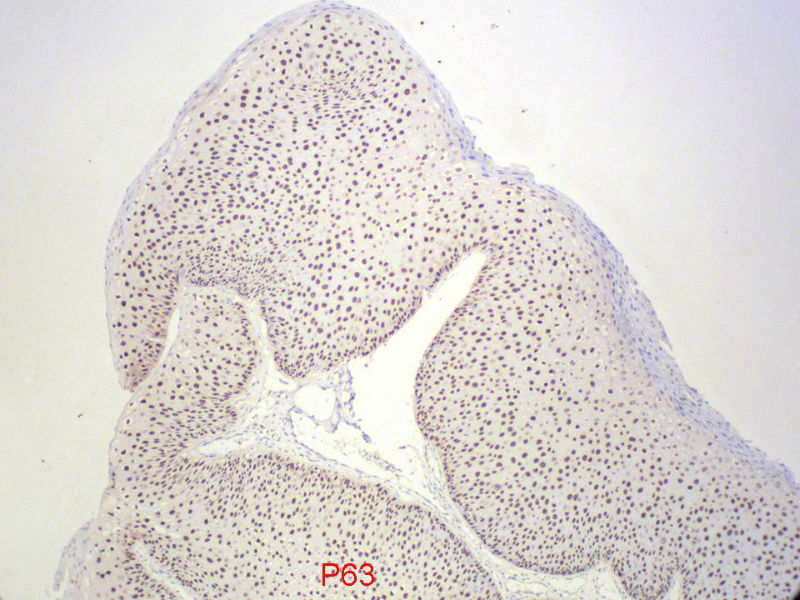

男,72岁,右耳听力下降两个月,检查右外耳道有黄豆大肿物,表面乳头状,手术切除。

您看了这样的免疫组化结果,会有什么样的考虑呢?